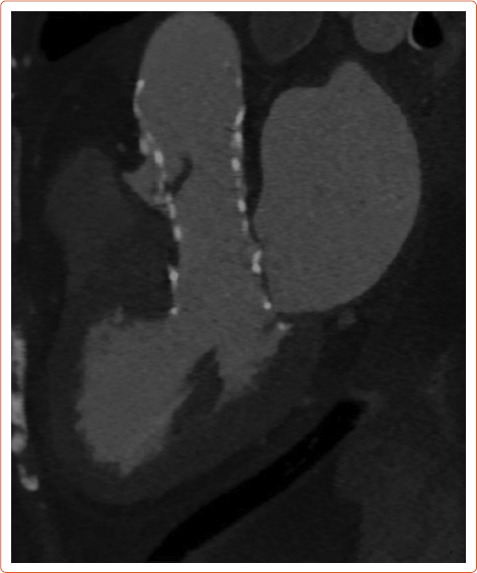

近年来,经导管主动脉瓣植入术患者发生亚临床小叶血栓形成(SLT)的现象越来越重要。CT诊断的低衰减小叶增厚和影响运动的低衰减是SLT的标志,其发生率随筛查强度而变化。这些现象是否代表小叶血栓形成,降低瓣膜耐久性和增加中风风险仍然是一个有争议的问题。TAVI后的最佳抗血栓治疗仍不确定,最佳治疗策略仍未确定。正在进行和未来的试验将为预防和治疗SLT的最佳策略提供更多证据。

In recent years, the phenomenon of subclinical leaflet thrombosis (SLT) in patients who have undergone transcatheter aortic valve implantation has become increasingly relevant. Hypo-attenuating leaflet thickening and hypo-attenuation affecting motion diagnosed by CT are the hallmarks of SLT, and their incidence varies depending on the intensity of screening. Whether these phenomena are a surrogate for leaflet thrombosis reducing valve durability and increasing the risk of stroke is still a matter of debate. Uncertainty remains over the optimal antithrombotic therapy after TAVI and the best treatment strategy is still not confirmed. Ongoing and future trials will provide more evidence about the best strategy for the prevention and treatment of SLT.